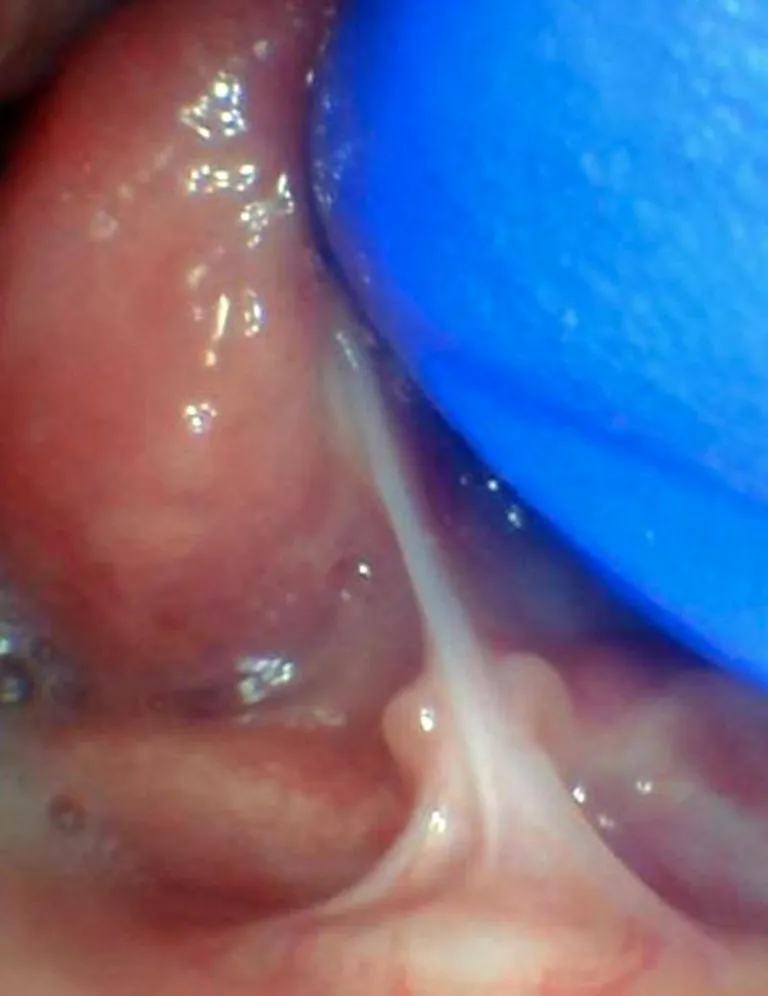

Le frein labial restrictif correspond à une anomalie où la lèvre supérieure est restreinte et ne peut pas bouger normalement. Il peut rendre difficile l'allaitement, l’alimentation, la parole et le brossage des incisives supérieures ; il peut également entraîner un diastème important (espace entre les dents) lorsqu’il est plus large que 2mm.

Il existe des spectres de restriction (site Tongue-Tie Alabama du Dr R. Baxter, Spectrum of lip/tongue restriction in infant/children), il n'existe pas une seule apparence. Il est donc important de comprendre la notion de symptomatique versus asymptomatique : un frein qui semble court ne sera opéré que s'il impacte la bonne fonction linguale, labiale ou jugale.

Photos ci-dessous issues du site Tongue-Tie Alabama avec l'accord de R. Baxter.

Enfant - Spectre de restrictions d'un FR labial